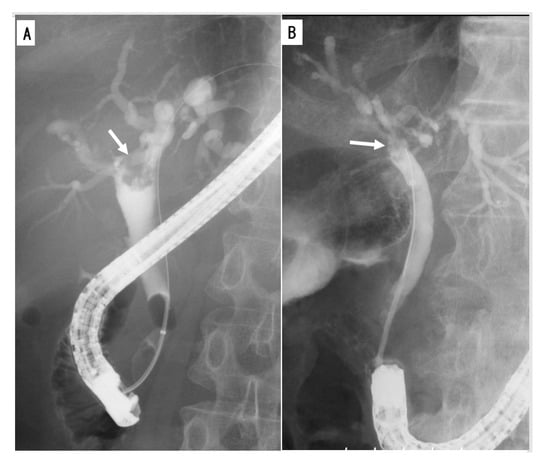

3.3.1. General Features

3.3.2. Four Subtypes

4.1.1. Type 1

4.1.2. Type 2